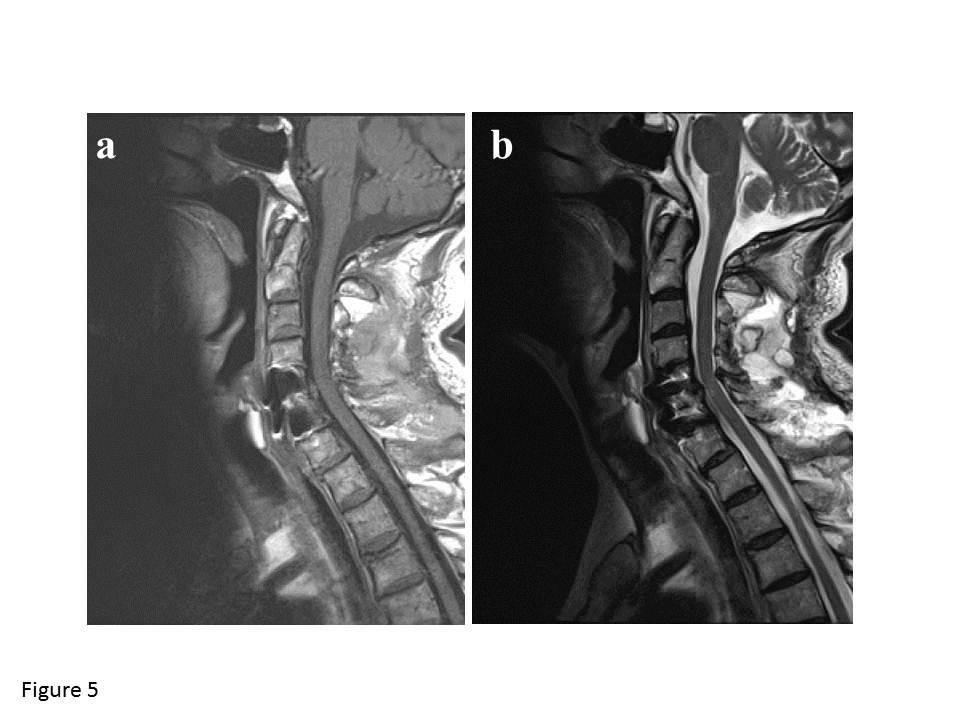

From jmedicalcasereports.biomedcentral.com

Delayed surgical treatment for a traumatic bilateral cervical facet Facet Joint Dislocation introduction and background. Find out how doctors diagnose and treat facet joint. Facet joint dislocations secondary to flexion distraction injury. the surgical treatment of lower cervical facet dislocation is controversial. the “reversed hamburger”, “naked facet” and “headphones” signs represent cervical facet joint dislocations. traumatic dislocations of facet joints are usually unstable injuries that require internal reduction,. Facet Joint Dislocation.